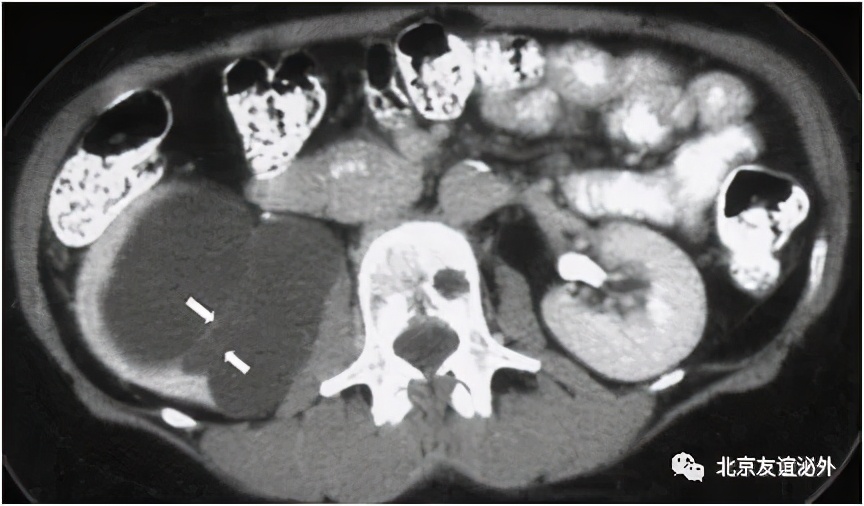

图2. Bosniak I级恶性囊肿(肾透明细胞癌),临床极为少见